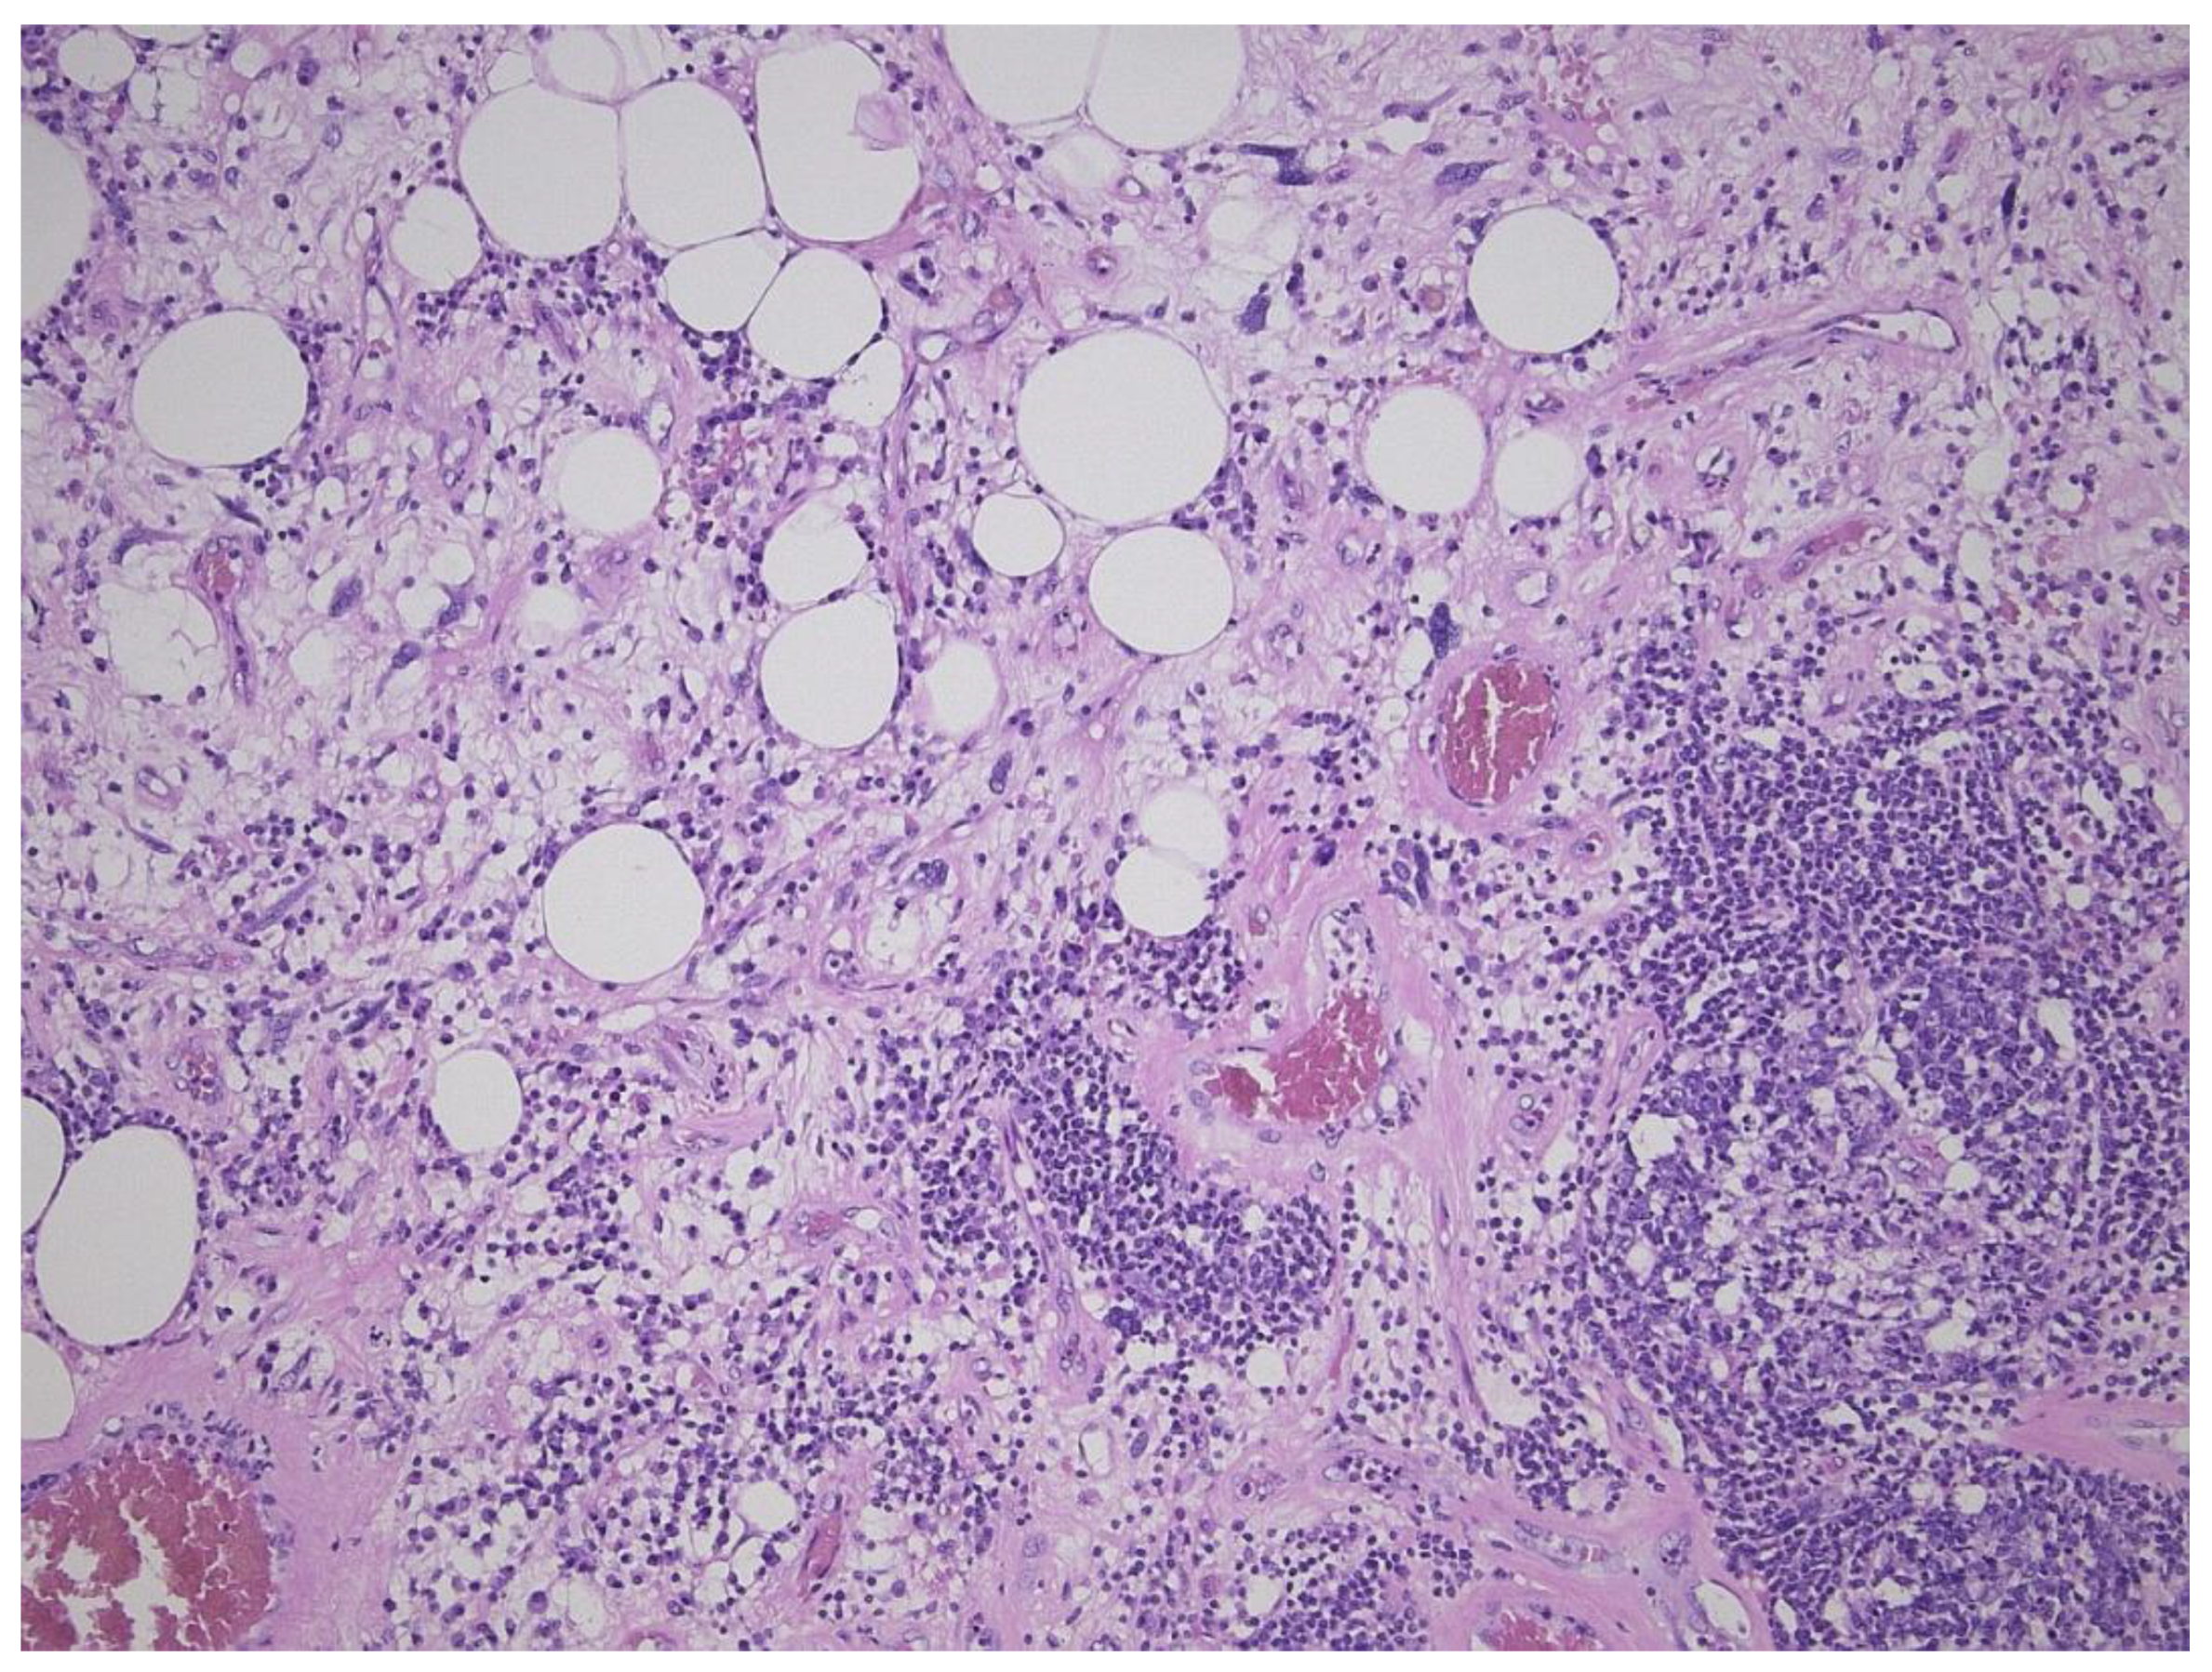

2. Well-Differentiated Liposarcoma/Atypical Lipomatous Tumor (WDL/ATL)

3. Dedifferentiated Liposarcoma